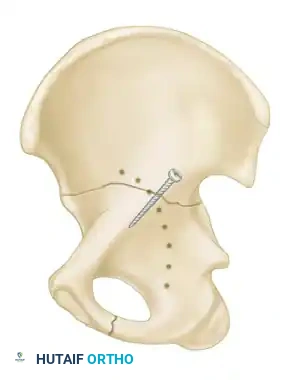

- Transverse Fractures: A single fracture line crosses both the anterior and posterior columns horizontally, dividing the innominate bone into a superior (iliac) segment and an inferior (ischiopubic) segment.

- Transverse and Posterior Wall: A transverse fracture with an associated posterior wall fracture. This is a highly unstable pattern often requiring a posterior surgical approach.

- T-Shaped Fractures: A transverse fracture with an additional vertical fracture line that splits the inferior ischiopubic segment, exiting through the obturator ring.

- Anterior Column and Posterior Hemitransverse: An anterior column fracture combined with a transverse fracture through the posterior column.

- Both-Column Fractures: The most complex pattern. All articular segments are detached from the intact posterior ilium (which remains attached to the sacrum).